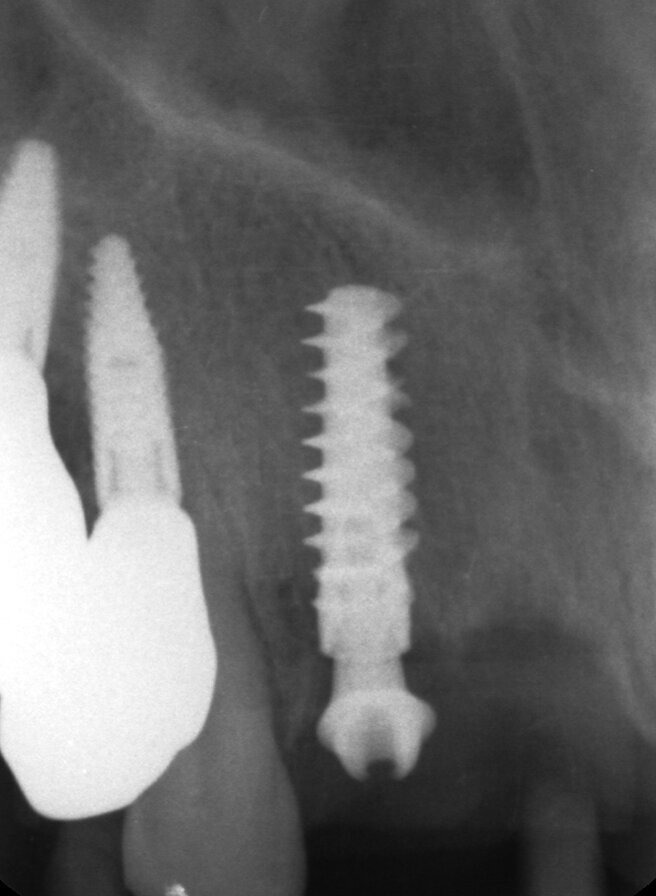

Il piano di trattamento prevede l’estrazione degli elementi dentali, l’inserimento di due impianti e la realizzazione di una protesi fissa di quattro elementi. Il problema da gestire è quello della fase provvisoria. Non è ipotizzabile una protesi mobile e quindi programmiamo di inserire subito dopo l’intervento un provvisorio immediato. Questo ci consente di condizionare da subito i tessuti periimplantari e anche le zone dei ponti. Si rileva un’impronta digitale (Figg. 5, 6), e la programmazione degli impianti viene effettuata con un software di chirurgia guidata (Fig. 7) e la posizione degli impianti nello spazio biologico e nello spazio protesico viene fatta sulla base di una ceratura diagnostica (Figg. 8, 9). Inseriamo gli impianti virtuali nell’osso disponibile (Figg. 10-13) e in relazione all’aspetto protesico correggiamo l’asse di inclinazione degli impianti con componenti secondarie angolate a 17° (Figg. 14, 15). Questo ci consentirà di realizzare una protesi avvitata con i fori situati nella zona palatale.

Fig. 10 - Posizionamento virtuale dell’impianto 1.2.

Fig. 11 - Posizionamento virtuale dell’impianto 2.2.

Fig. 12 - Cross impianto 1.2.

Fig. 13 - Cross impianto 2.2.

Il nostro obiettivo è quello di riuscire a dare alla paziente un provvisorio immediato nell’arco di due ore. Questo diventa possibile perché abbiamo utilizzato un flusso digitale fin dall’inizio. In laboratorio vengono realizzate la dima chirurgica (Figg. 16, 17), la dima protesica (Fig. 18) e anche il provvisorio (Figg. 19-21) che contiene delle alette di riposizionamento. Il tutto gestito con modelli digitali sui quali saremo in grado di funzionalizzare il provvisorio post-chirurgico (tecnica DIL). In un caso come questo se utilizziamo un flusso digitale possiamo evitare subito dopo la chirurgia di rilevare un’impronta degli impianti inseriti. Infatti, utilizziamo una dima chirurgica che ci faciliterà le fasi di intervento. La dima ci consentirà di non fare lembi e nessuna incisione di rilascio (Fig. 22), dopo aver inserito gli impianti (BLX Straumann) (Figg. 23-31) e aver controllato il loro alloggiamento, inseriamo sugli stessi dei transfert da impronta (Fig. 32).